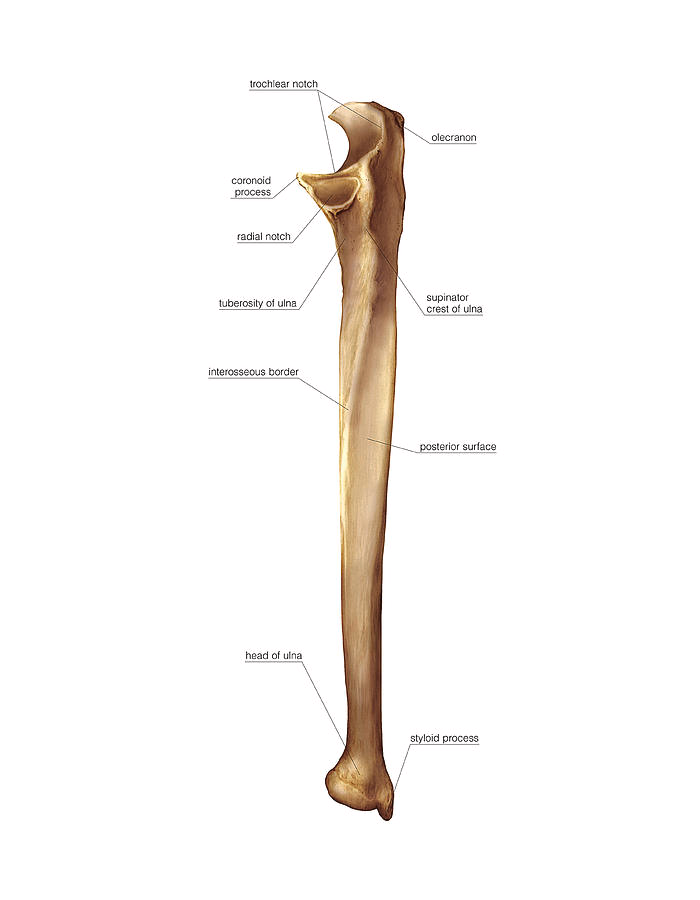

Ulnar(left?)